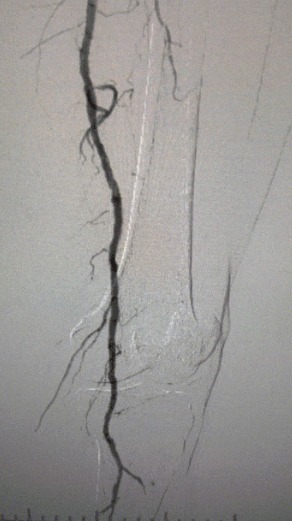

Résultats cliniques

· Examen physique: Impulsions fémorales faibles; pulsations absentes de poplité et de dorsalis pedis; ulcération sur le premier orteil gauche; nécrose sur le premier et le deuxième orteils droits

· Imagerie préopératoire: sténose calcifiée diffuse sévère dans les artères bilatérales des membres inférieurs

Résultat chirurgical

Après la procédure, la sténose artérielle s'est améliorée de manière significative, le flux sanguin a augmenté et la température de la peau a augmenté. Aucune complication postopératoire n'est survenue. Le patient et l'équipe chirurgicale étaient très satisfaits des résultats.